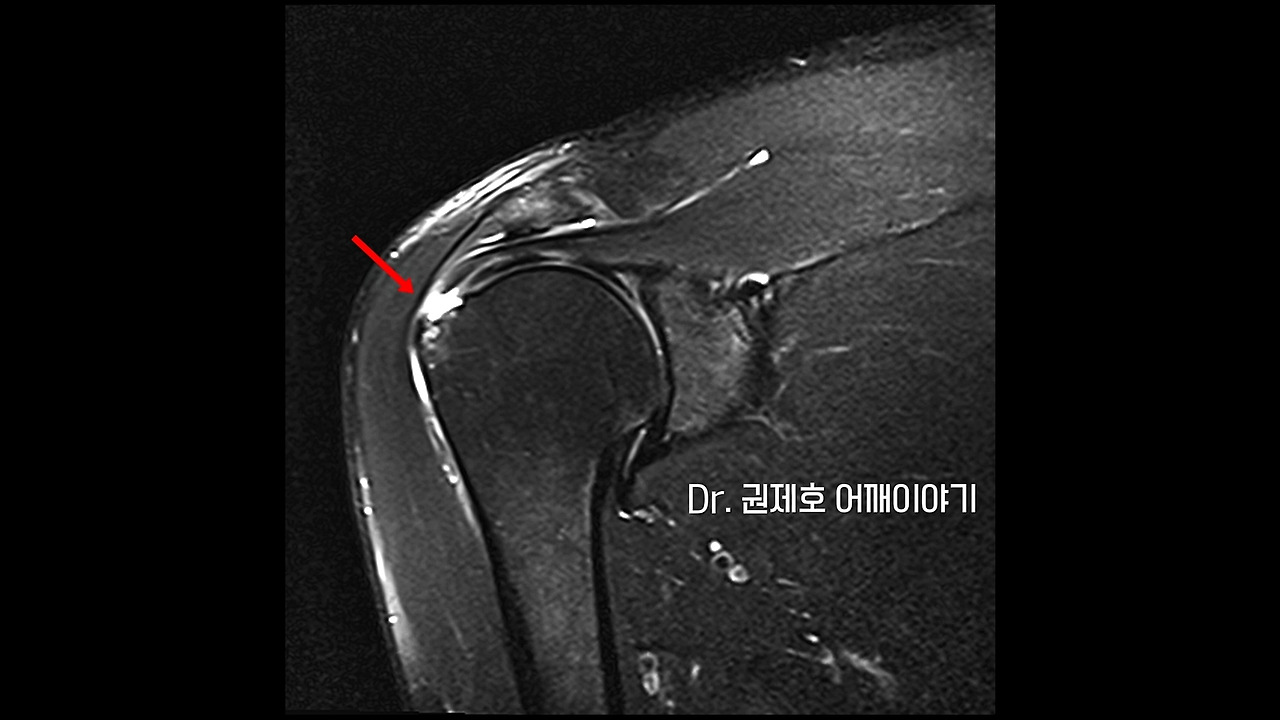

MRI를 보는 이유는 모든 것을 보기 위함입니다. 위에서 화살표 방향을 보면 알겠지만 검은색의 끈 모양이 가는 중에 끝에서 흰색의 빈 공간이 생기는 것을 알 수 있습니다. 검은색으로 보이는 것이 어깨 인대이고, 끝에서 흰색 빈 공간이 생기는 것이 어깨 인대 파열을 의미하는 소견입니다. 즉 힘줄이 뼈에서 뜯긴 상황 혹은 끊어진 상황입니다.

간혹 검색을 하다 보면 '어깨 회전근개파열 비수술적 치료로~' 하는 문구를 볼 수 있습니다. 부분적으로 파열된 것은 당연히 비수술적 치료 방법으로 진행하는 것이 옳은 방법입니다. 하지만 위 사진처럼 완전 파열인 경우에는 수술적 치료만으로만 인대를 다시 붙일 수 있으며, 기능 회복을 위해선 재활 역시 필요합니다. 부분 파열도 파열이기 때문에 그런 글들을 많이 볼 수 있습니다만, 내 어깨 상태가 어떤 상황인지를 아는 것이 더욱 중요할 듯합니다.